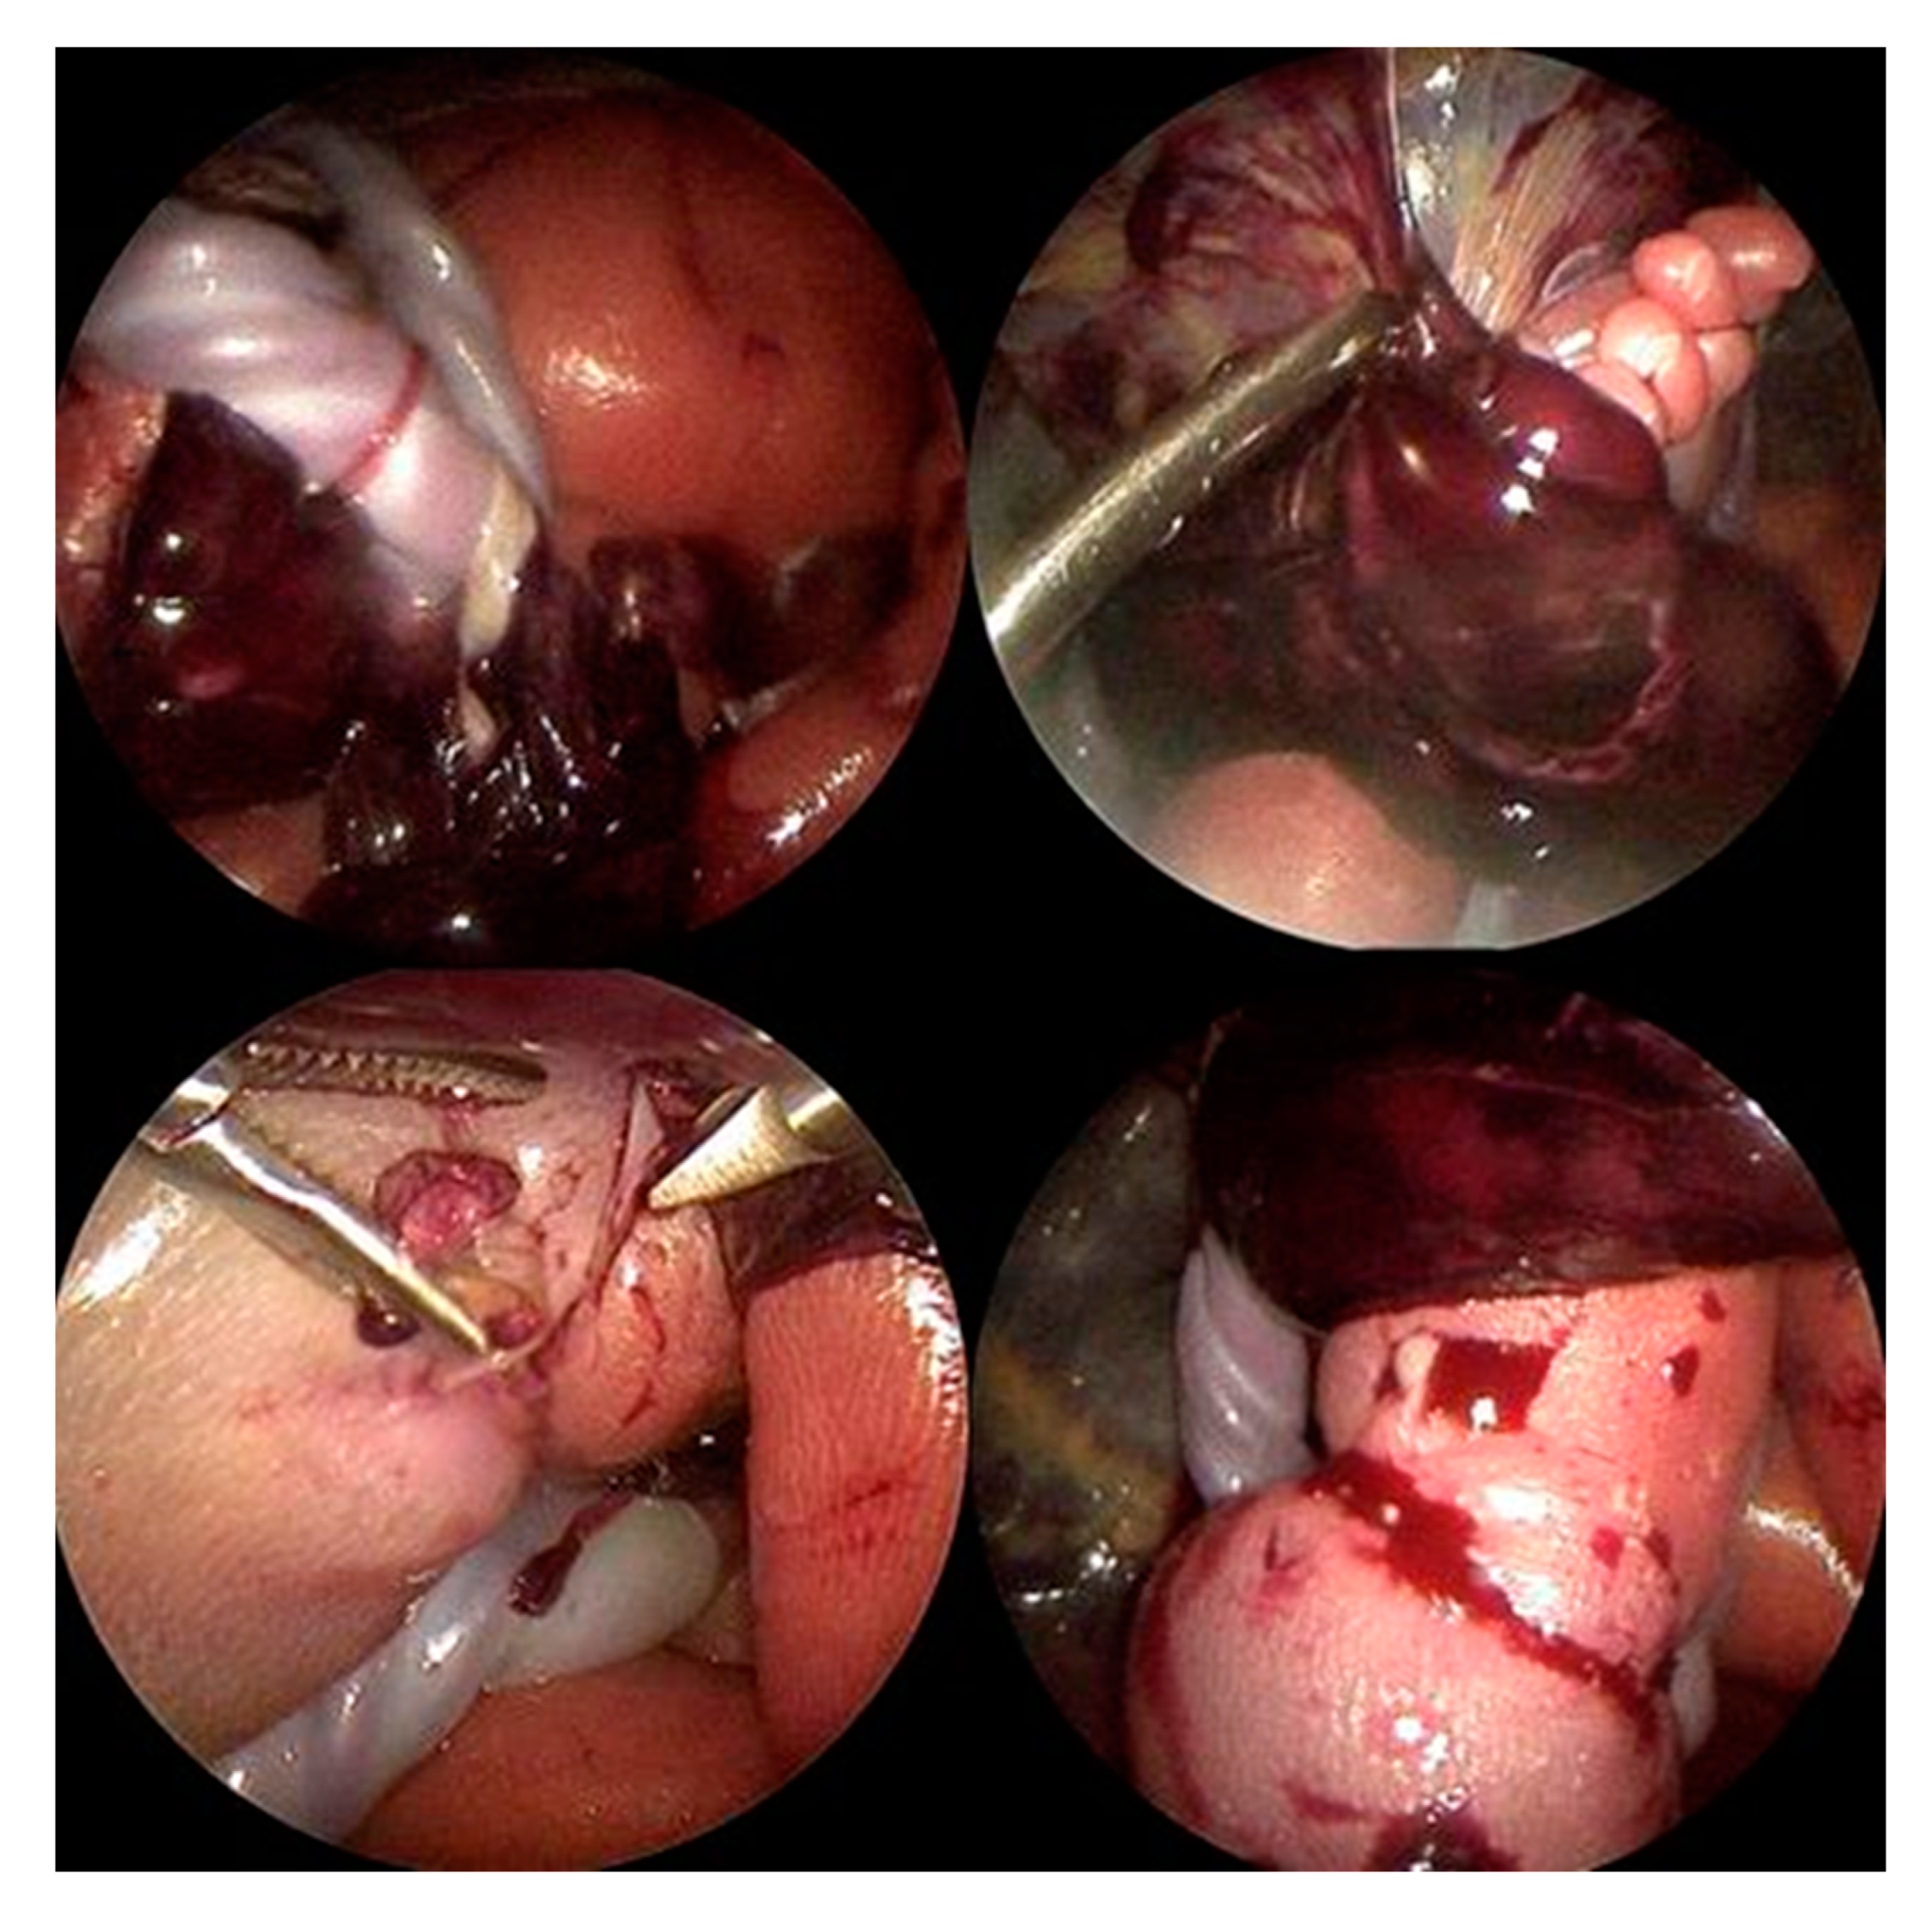

As already suspected in the ultrasound examination, the fetus was seen to lie in a blood-tainted amniotic cavity covered by amniotic material (Figure 3). As the left foot was protruding through a hole in the abrupted placenta, the fetus might have torn it off with a wrong movement, which, in the worst case, could have resulted in severe maternal hemorrhage. The umbilical cord was surrounded by multiple strings of the detached amniotic sac, and the proximal right calf was constricted by a tight, circumferential amniotic band (Figure 4).

Visualized by a 3.3 mm 30-degree rod-lens fetoscope, all amniotic bands, as well as the abrupted placental segment, were dissected using endoscopic scissors and graspers (Figure 4). Following dissection of the band that strangulated the proximal right calf, the extremity distal to the constriction quickly turned pink again, heralding promise for its preservation.

Figure 4. Top left: Multiple annular amniotic bands were entangling the umbilical cord and placental tissues. Top right: The fetal left foot was stuck within a part of the placenta, both restricting fetal movement and placing the mother and fetus at high risk of hemorrhage. Bottom left: A tight amniotic band encircling the right fetal calf caused severe strangulation, which would have led to partial limb autoamputation if left unresolved. Bottom right: After dissection of the right leg constriction due to the amniotic band, blood flow to the calf and foot improved immediately.